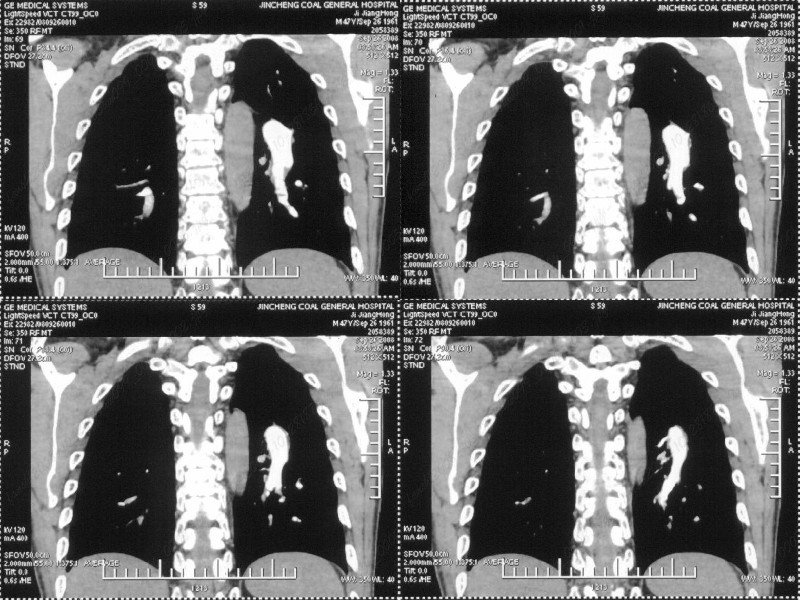

男性,47岁。胸部不适一年,ct检查发现右胸膜下结节。http://www.radida.com/bbs/forum.php?mod=viewthread&tid=46094

考虑右下胸膜的炎性结节,

右下肺胸膜下小结节,强化不明显。建议定期观察!

汇报临床诊断:右肺动脉分枝栓塞

考虑心脏疾患引起的右侧斜裂增厚。

右肺静脉充盈缺损,左心房体积小,右肺动脉远端动脉充盈缺损,右肺血管影细小,考虑;右肺动脉远端栓塞.